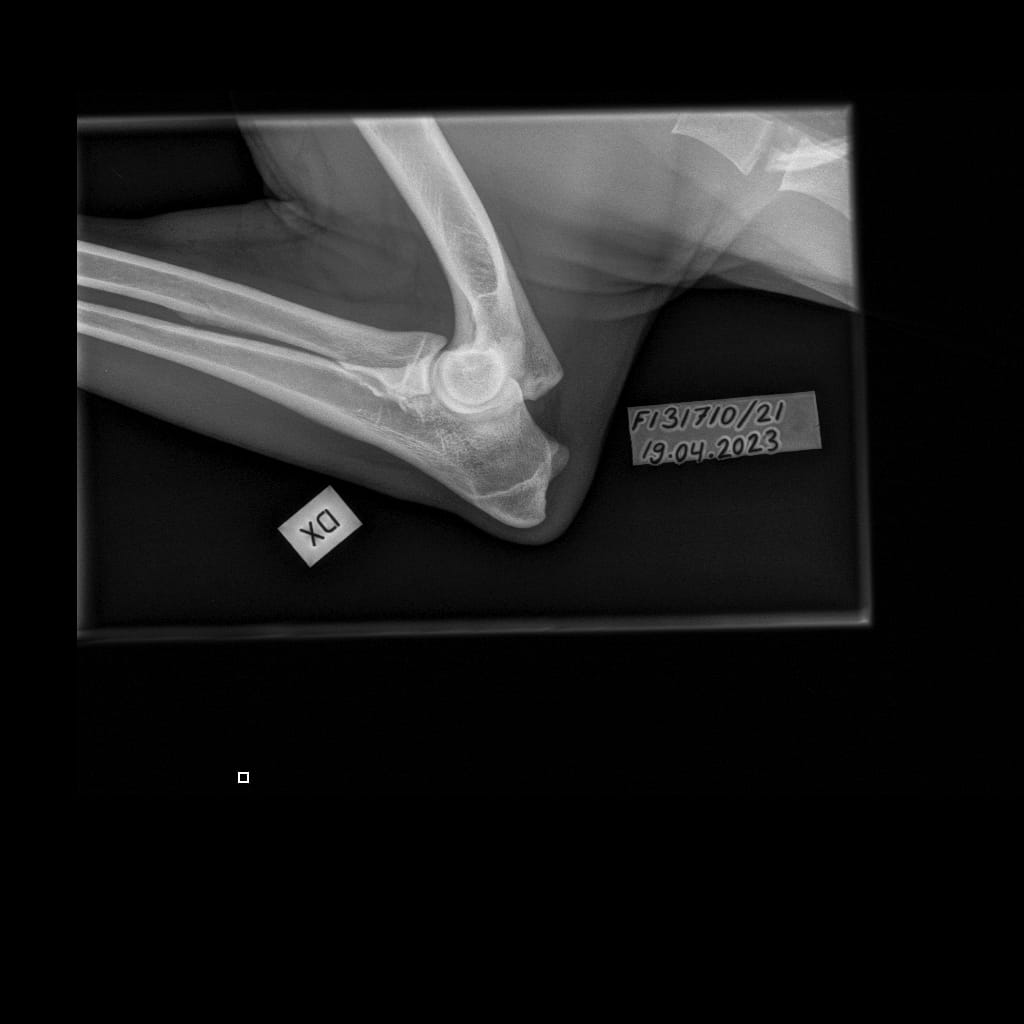

| Lumottu Martta Iivontytär ft. Finnridge | Lime ♀︎ | 525 g | Correct | TBA | TBA | TBA | A/A | Xray: 0/0 CT: 3/1 | Unaffected/Open to interpretation | LTV0, SP0, VA0 | MH, unfamiliar to gunshot | |

| Elbows: | 0/0 (xray), 3/1 (CT) |

| Shoulders: | Unaffected/Open to interpretation |